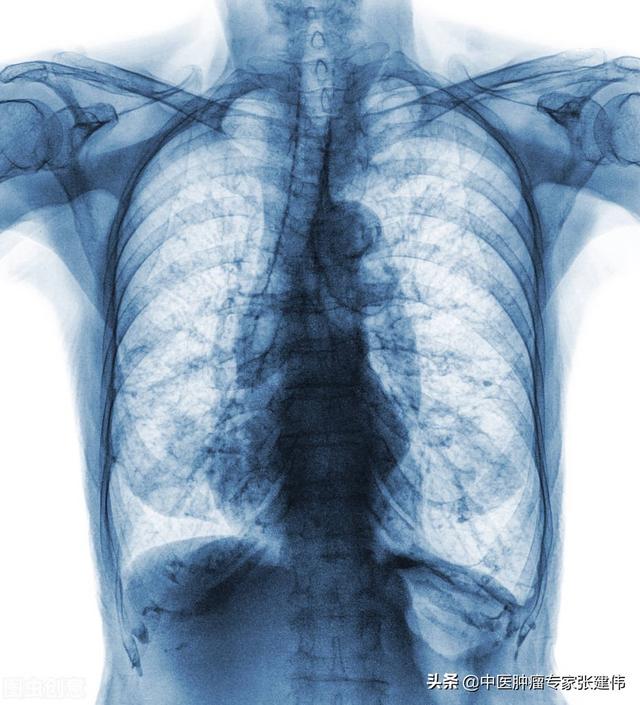

現在では、CT検査で肺に線維性病巣や石灰化病巣を見つけることは比較的日常的に行われている。 一般に、限局した筋状病巣や石灰化病巣は、その場所が古い病変であることを示しており、下図は左肺尖部に石灰化病巣を認めた患者の典型的なCT画像である。

肺の線維化病巣や石灰化病巣をチェックする最も効果的な方法は、胸部レントゲンや胸部CTを撮ることだが、もちろん胸部CTの鮮明さや精度はレントゲンより高く、値段も少し高い。